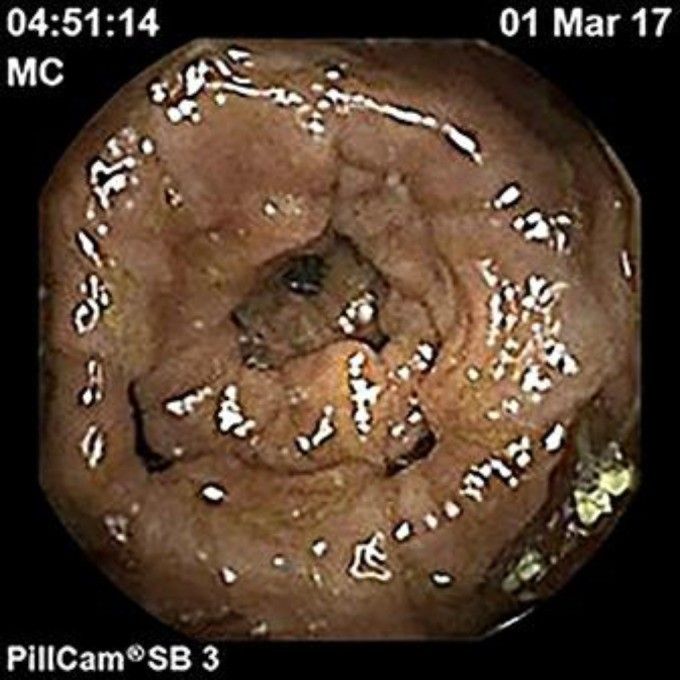

При селективной ангиографии признаков артериовенозных мальформаций не выявлено. Капсульная эндоскопия подтвердила все вышеизложенные результаты и дополнительно показала варикозные расширения во всей тонкой кишке с максимальной выраженностью в подвздошной (рис. 4). На основании всех этих обследований были исключены любые причины варикозного расширения вен тонкой и толстой кишок, вызванные изменениями магистральных сосудов.

Рисунок 4 [1].